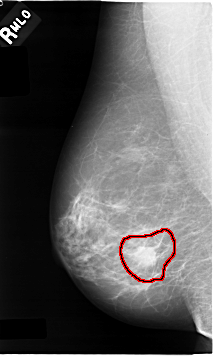

C_0009_1.RIGHT_MLO

FILE: C_0009_1.RIGHT_MLO.OVERLAY

TOTAL_ABNORMALITIES 1

ABNORMALITY 1

LESION_TYPE MASS SHAPE IRREGULAR MARGINS SPICULATED

ASSESSMENT 5

SUBTLETY 5

PATHOLOGY MALIGNANT

TOTAL_OUTLINES 1

BOUNDARY